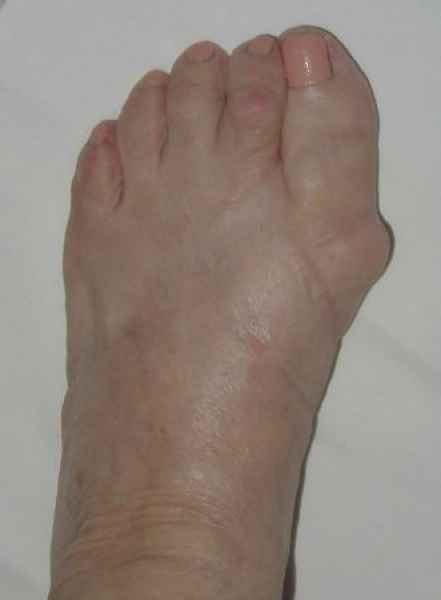

La marcha no solo es característica de la especie humana sino también de cada persona, y más aún varía según el estado de ánimo del momento. Una patología en los pies, se traduce en el rostro, en el ánimo, en el psiquismo. No sólo el dolor produce estos efectos, también un pie deformado o poco estético. En nuestra sociedad, la estética constituye un valor muy apreciado y estas alteraciones causan vergüenza fundamentalmente en las mujeres, que esconden en la playa sus pies en la arena y no pueden usar calzados elegantes.

Tanto la estructura del pie como su funcionalismo que es la marcha, pueden ser asiento y manifestación respectivamente de alteraciones locales ó sistémicas, por lo que su cuidadoso examen resulta de extrema utilidad diagnóstica.